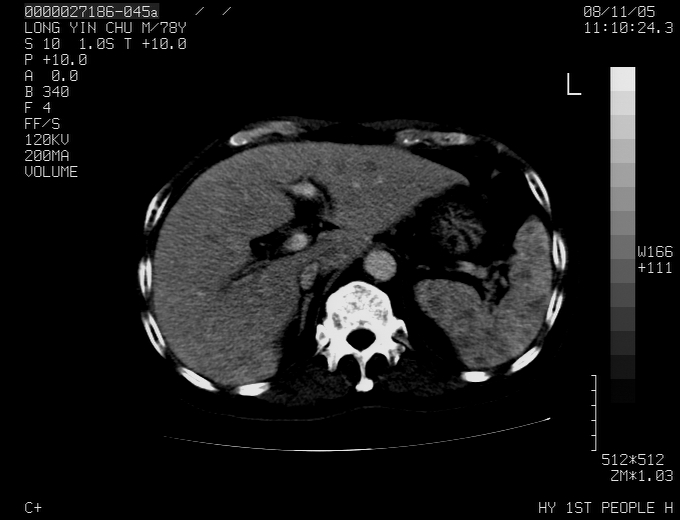

标题: CT16532:M78Y,肝脏病变,请会诊 [打印本页]

标题: CT16532:M78Y,肝脏病变,请会诊

腹胀,腹痛就诊,男性,78岁,外院b超未见异常。

肝ca,脾肾转移

考虑弥漫性肝癌并脾及双肾转移.双侧胸水.

图片质量欠佳:多考虑:左侧肾癌。脾脏转移!胸膜转移!

肝脾肾转移瘤可能性大,左肾不除外梗塞,双侧胸水

考虑弥漫性肝癌并脾及双肾转移,双侧胸水。